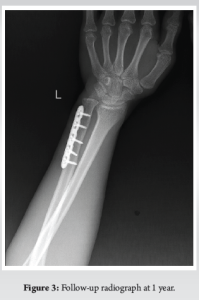

Radiographs of the elbow were also done which was normal The patient was prepared for operative intervention and necessary investigations were done. The subcutaneous approach was used and open reduction internal fixation was done using standard low-contact dynamic compression plate (Fig. 2). Distal radioulnar joint was reduced with the help of a pointed reduction clamp and a 2 mm k wire was inserted from ulna to radius. The challenge faced during this case was the reduction of radioulnar joint after ulna fixation. Radial deviation with traction and countertraction was done to reduce the DRUJ. We initially tried to reduce DRUJ first and fix the ulna afterward with holding the DRUJ using a reduction clamp but was not possible. So we fixed ulna first and reduced DRUJ later on. Postoperatively, the wrist was immobilized for 4 weeks. The K-wire was removed after 4 weeks. The gradual physiotherapy with wrist range of motion and grip strengthening exercises were started. Wrist range of motion was fully achieved in about 8 weeks and grip strength was also within preoperative status by 10 weeks. After that, all normal activities were allowed to patient which was done preoperatively by the patient. He was followed up at 2 weeks, 4 weeks, and then monthly thereafter. After 1 year of follow-up, the fracture has healed completely (Fig. 3) and had a satisfactory range of motion (Table 1). He was able to carry out his activities of daily living comfortably and his Disability of the Arm, Shoulder, and Humerus of the (DASH) [5] score was calculated to be 19.2.